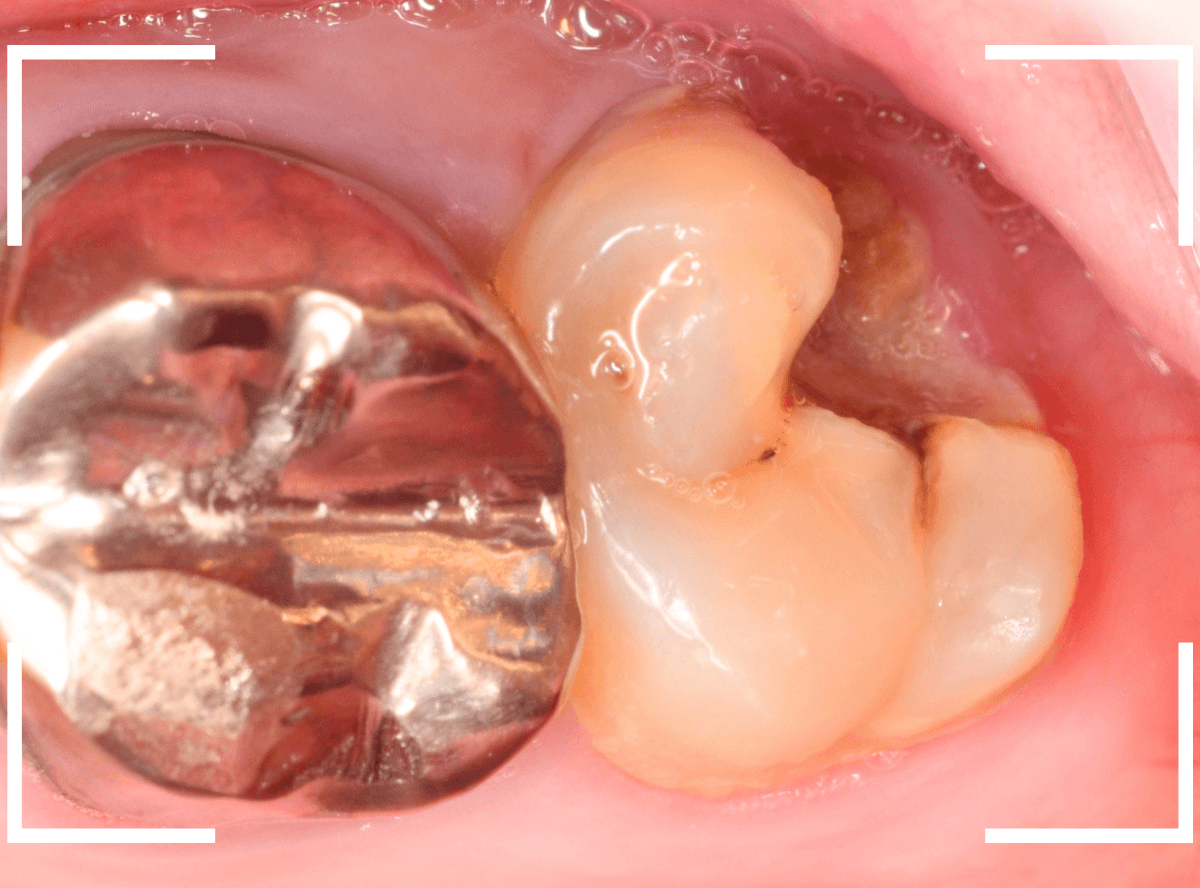

Case.18 おやしらずの抜歯後に歯がしみる

今回は、上のおやしらずが原因で虫歯になってしまった方のケースです。

〇部のおやしらずを虫歯で抜歯しました。

抜歯してしばらく経ったところです。

特に問題なさそうに見えますが、「おやしらずを抜歯してから、歯がしみるようになった」との訴えです。

これは、おやしらずを抜歯した後によくある症状です。

レントゲン写真で確認します。

青い線が歯の神経、赤い線が虫歯です。

おやしらずがあった際にはわかりづらかったですが、歯の後ろ側のおやしらずが重なっていたところが虫歯になっているのがわかります。

おやしらずが原因で、このように手前の歯が虫歯になってしまう事が多いために、抜歯を勧められる事が多いのです。

そして、虫歯の部分におやしらずが被さっていたために、しみる症状などを感じなかったのです。

金属を外したところです。

写真では写ってしませんが、この奥に虫歯があります。

全ての虫歯を除去したところです。

抜歯した後ろのおやしらずは、元々虫歯の治療がしてありましたが、その際に抜歯しておいた方が良かったのではないかな、と思いました。